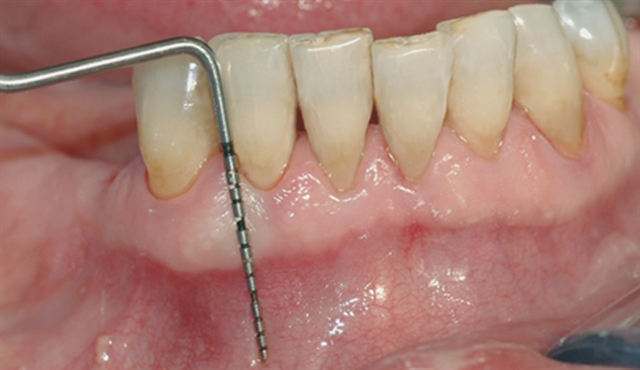

• perio stor 3

perio stor 3

Instrumentet er her lagt utenfor tannkjøttet for å vise hvor stort festetapet egentlig er.